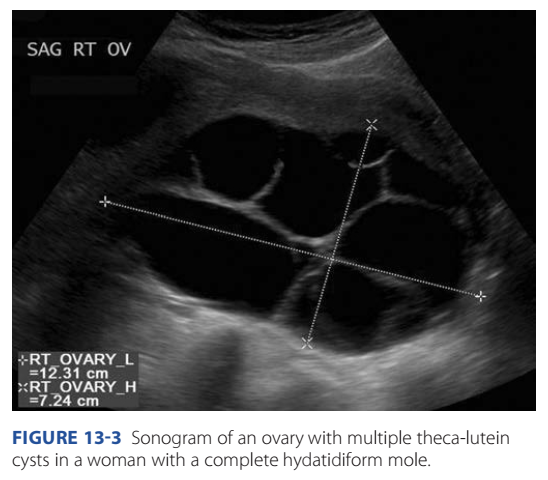

rom multiple theca-lutein cysts (Fig. 13-3). Tese are more

common with a complete mole and likely result rom ovarian

overstimulation by excessive hCG levels. Remember that hCG

and luteinizing hormone share the same receptor, and both can

stimulate the theca layer that surrounds ollicles. Because thecalutein cysts regress ollowing pregnancy evacuation and subsequent hCG level decline, expectant management is preerred.

FIGURE 13-3 Sonogram of an ovary with multiple theca-lutein cysts in a woman with a complete hydatidiform mole.